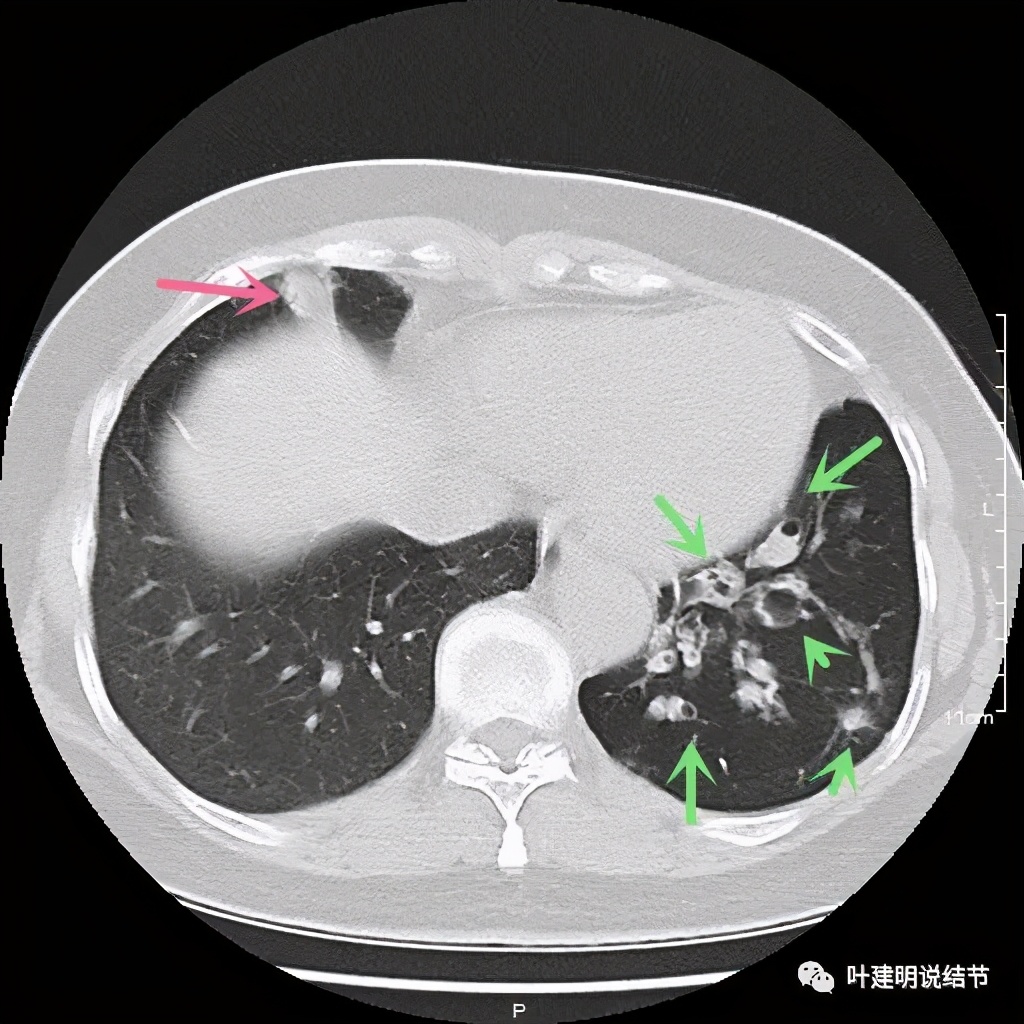

其实若从以上影像上看,恶性还真不能除外的,相对来说,恶性的可能应该大于良性。但看肺结节,我们在看细节特征的同时,还要看其他肺野有没有异常,综合来考虑。因为她的左下肺其他部位有病变存在,先来看下图像:

左下肺野多发支气管扩张呈囊状,也有一些实性密度的结节(考虑扩张支气管内的痰栓)。右侧也有实性炎性病灶。所以综合来看,左下之前的结节也得考虑与这些同源,一个原因来解释更为合理,所以恶性的可能性又小了。我建议其随访观察。昨天来复查,我们来看下这次的CT图像: